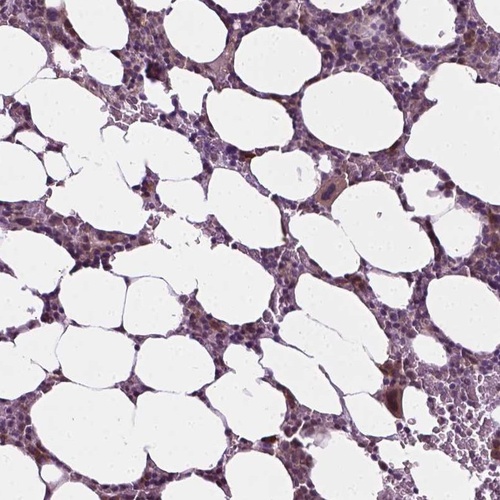

Immunohistochemical staining of human bone marrow shows moderate nuclear positivity in hematopoietic cells.